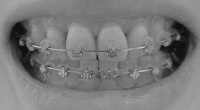

前から見たところ。特に変化なし。

2008/5/20撮影